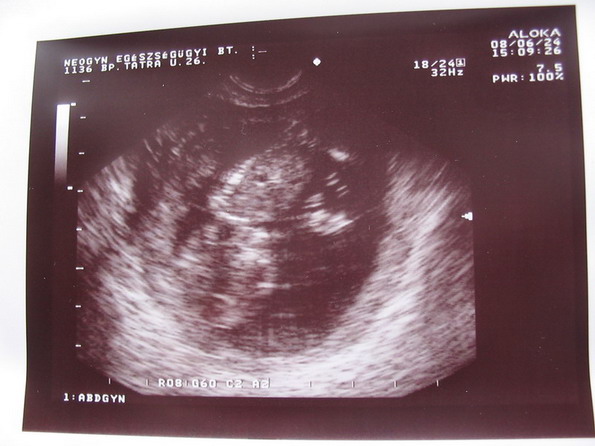

Marietta, szép pocak

Ma én is dobok egy képet, de legyen elég előre annyi, hogy 120 cm a haskörfogatom